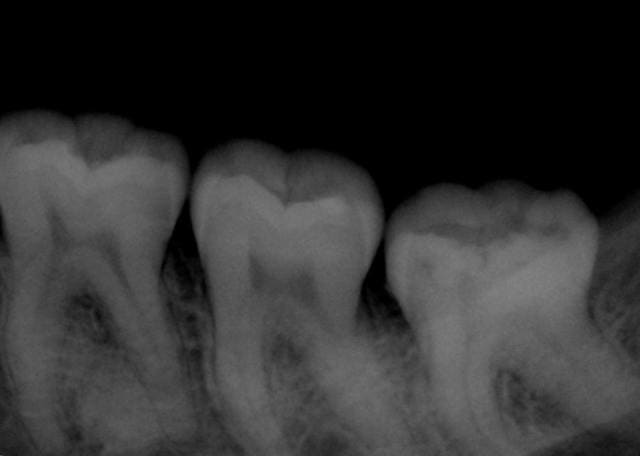

Patiente, 25 ans, dents impeccables, juste une sensation un peu douloureuse secteur 3 à la mastication depuis quelques jours.

Image assez "classique", ce qui m'interroge c'est la symptomatologie.

C'est l'image de condensation osseuse que je trouve "classique" pour ne pas dire fréquente mais généralement c'est asymptomatique, c'est ce qui m'étonne.

La question que je me pose c'est de savoir si l'image de condensation osseuse relativement classique peut avoir un rapport avec ces douleurs.

Rien de particulier à la pano, juste cette image osseuse bizarre.

Ce qui m'interroge depuis le début c'est l'image osseuse apicale... qui détourne peut être aussi mon jugement... :-)